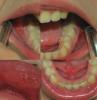

humanthe Опубликовано 3 июня, 2010 Поделиться Опубликовано 3 июня, 2010 За рание извеняюсь за свою не граматность, не учили меня русской грамоте. В обшчем проблема заключаетсо в том , что примерно с промежутками в 3-6 месецев уже на протежении 3 лет, восполяетса большая часть ротовой полости. Врочи увидев мое состояние гаворят о госпитолезацыи и разводят руками. Обычно в таких ситуацыях просыпаясь утром по непонятным мне причинам, залипают глаза, жолтые образования не дают открыть глаза, когда стоматит достигает пика, с утра не возможно открыть рот ииа образовавшейся на нём корки. Медикаменты прописывали разные - метрогель дента, ротокан, саногель (лично я им пользуюсь чтобе обезболить язвы и попить поесть так как в состав входит ледакаин), в последный визит у врача 3 стоматолога покрихтели надомной поохали и выписали 2 вида антибиотиков - бисептол как стондарт уже и какието ешчо не помню. Я человек куряшчий, проверял, 1 раз курил во время восполения второй раз не - всё осталось не изменным. Недели 2 держетсо ето всё у меня во рту лечи не лечи, по прошествию изчезает почти моментально за 1-2 дня.на фотографиях самое начало, со всех сторон развиваетсо одновременно. Есле ето чтото меняет то и у моей матери ест проблемы с етим но в гораздо меншей степени (раз в месеца 3 1 маленькая язва - убераетсо ротоканом) и у брата но у брата ешчо реже и тот отделываетсо зелёнкой. Проводился полный онализ крови врачами нарушенй не выявленою Ссылка на комментарий

humanthe Опубликовано 3 июня, 2010 Автор Поделиться Опубликовано 3 июня, 2010 (изменено) А как на счет пузырьков?В процессе заболевания появляется светобоязнь или ухудшение зрения? На фотографии в первом посте, в нижнем левом фрагменте, видно верхнию часть губы.Там, в лево от той язвы что по центру видно многочисленые водеистые пузерьки. Пресудствуют пузырьки только на губах, в осталных частях покраснения м язвы, без пузырьков, как мне призходилось наблюдать. Светобоязнь отсудствует. Ухудшение зрения присудствует в виде выделений и глаза, когда желеобразное вешчество наплуыает на зрачок, зрение затуманено. Как и должно быть при конюктевите, есле я не ошыбаюсь. Изменено 3 июня, 2010 пользователем humanthe Ссылка на комментарий